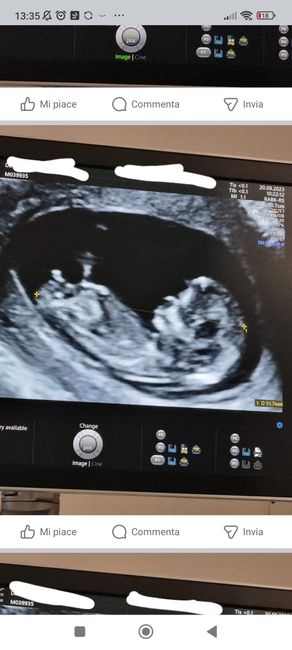

Ho caricato una foto nel post di Giada

920 giorni fa

Ciao, ci provo anch’io per curiosità 😊 Secondo voi si può già capire in qualche modo se femmina o maschio? Eco interna di ieri a 9 settimane. Grazie per chi vuol azzardare 😁